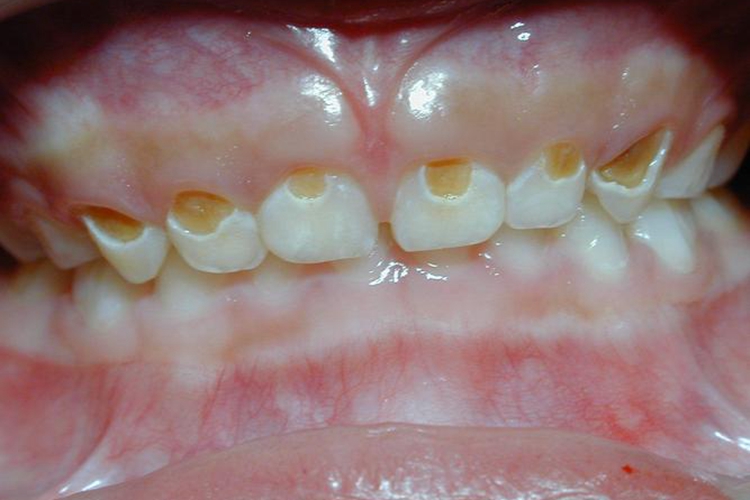

2岁宝宝牙釉质脱落严重主要表现为牙齿表面出现带状或窝状的棕色凹陷,可能是牙釉质发育不全导致,需尽快到口腔科就诊治疗。

重度牙釉质发育不全的患者,牙面可出现带状或者窝状的棕色凹陷,由于致病因素出现在牙发育期,故受累牙往往呈对称性。乳牙根尖周严重感染,可导致继承恒牙釉质发育不全。